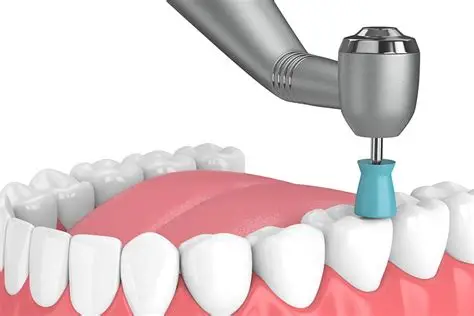

Scaling And Polishing

Refine your smile with a Deep Cleanse

Professional dental scaling and polishing removes stubborn plaque, tartar (calculus), and surface stains that regular brushing simply cannot eliminate. Our ultrasonic scaling instruments clean deep below the gumline, preventing gum disease and restoring your teeth’s natural brightness.

With Exceptional care through latest Pain Free technology

Scaling & Polishing isn’t just a dental procedure, it’s an entire feeling of change. Regular treatments help you stay free of dental issues, improve your breath, and keep your smile bright and confident